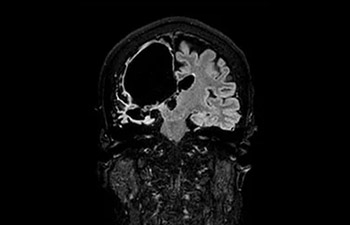

• Baanbrekende versnellingstechniek waarmee niet alleen sequenties versneld worden, maar uw gehele MRI-onderzoek. • Unieke implementatie waarmee 2D- en 3D-scans tot wel 50% sneller gemaakt kunnen worden met een nagenoeg gelijkwaardige beeldkwaliteit.1

• Kan gebruikt worden in alle anatomische contrasten en alle anatomieën.

met Compressed SENSE